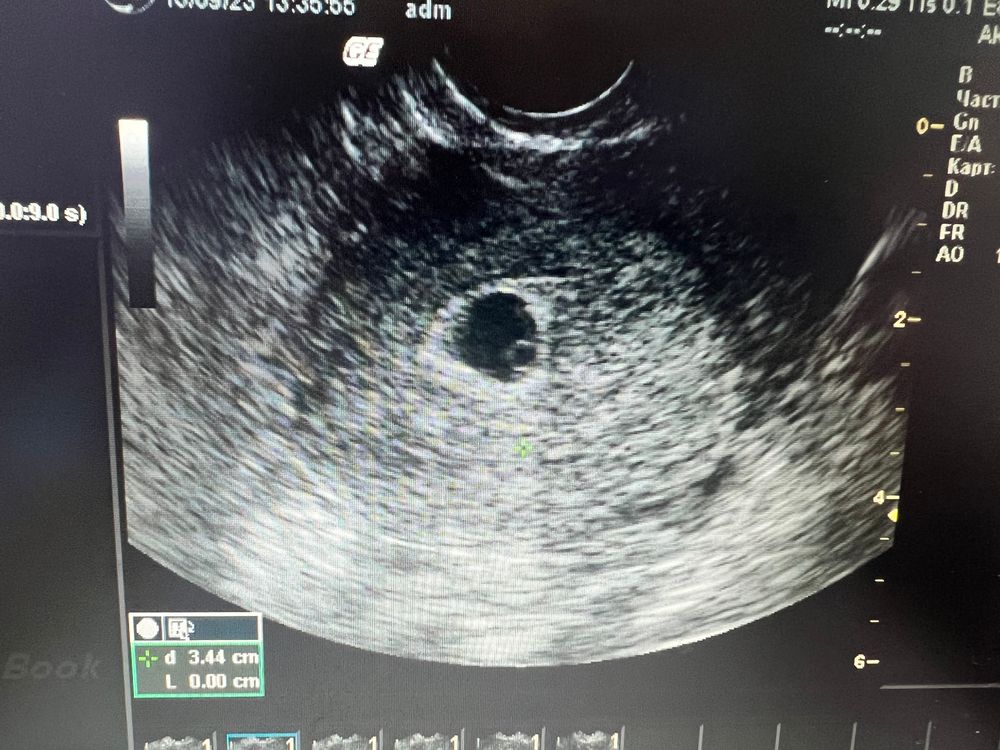

УЗИ 5 недель 5 дней

ПЯ 10мм, ЖМ 3,1 мм, ЖТ 13,5мм

эмбриончика пока не увидели. Только желточный мешочек. Врач сказала что пока рано, это так?

По узи размеры плодного яйца где то на 5 недель, но врач сказала это не показатель. Сказала через 1.5 недели теперь прийти )) вот такие дела